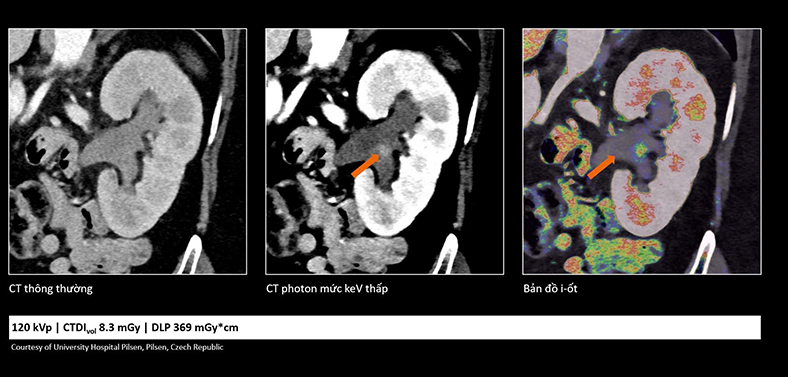

So sánh cho thấy công nghệ cắt lớp vi tính lượng tử không chỉ giúp hình ảnh rõ hơn mà còn cung cấp thêm thông tin, hỗ trợ bác sĩ đánh giá tổn thương chính xác hơn - Ảnh: DNCC

Trong ung thư, việc phát hiện sớm những tổn thương rất nhỏ đóng vai trò quan trọng trong hiệu quả điều trị. Công nghệ cắt lớp vi tính lượng tử cho phép tái tạo hình ảnh với lát cắt rất mỏng (tới 0,2 mm), giúp phát hiện những bất thường mà trước đây có thể bị bỏ sót.

Nhờ đó, bác sĩ có thể nhận diện sớm các dấu hiệu bất thường và đánh giá chính xác hơn đặc tính tổn thương, hỗ trợ hiệu quả trong chẩn đoán sớm cũng như theo dõi tái phát.